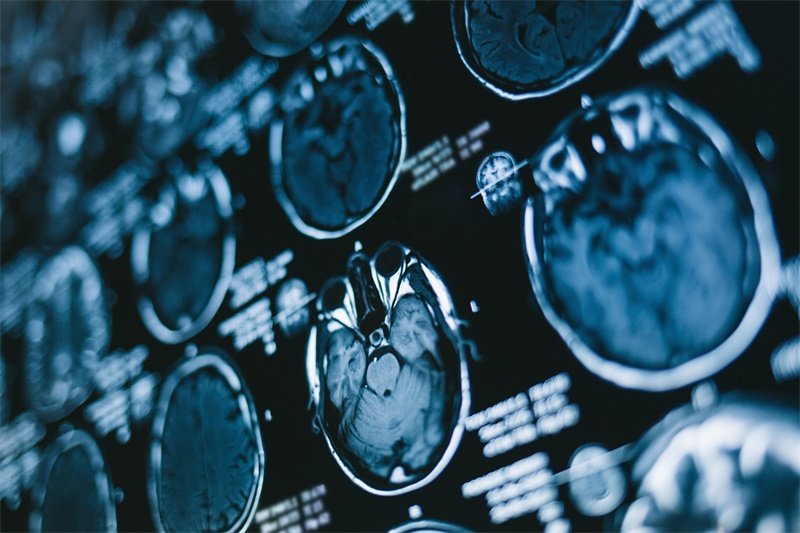

影像学检查

影像学检查是确诊鼻子蝶骨囊性占位的重要手段,CT(计算机断层扫描)和MRI(磁共振成像)都是比较常用的检查方法。

CT扫描可以清晰显示囊性占位的位置和大小,而MRI则提供更丰富的组织信息,对于评估影响周围结构的程度尤为重要。